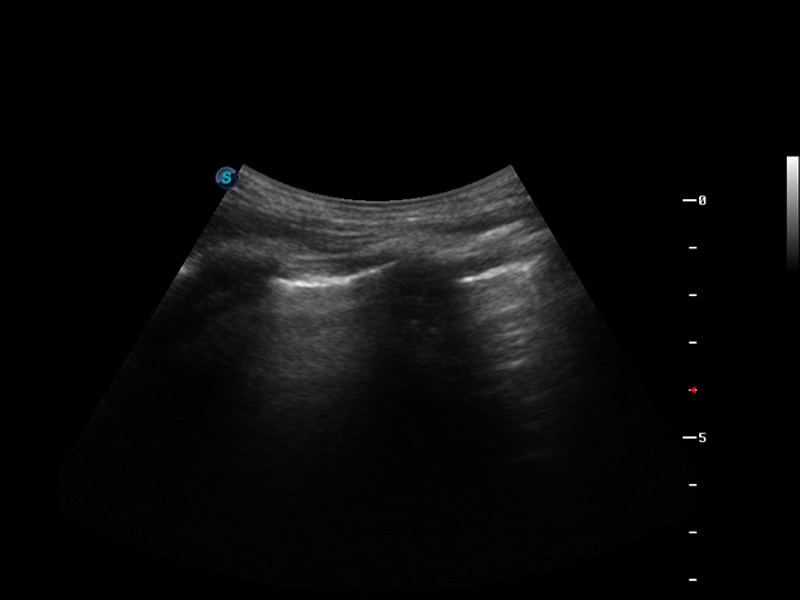

S9便携式彩色多普勒超声诊断仪是球速体育入口研发的高端便携彩超设备,外观设计新颖、产品性能卓越。S9在便携超声领域采用了突破传统的触摸屏交互设计,并以先进的软件硬件技术和设计理念,为您带来清晰的图像质量、稳定的工作性能和便捷的操作体验。

脉冲反相谐波成像